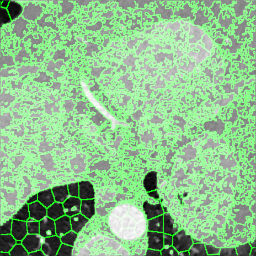

We extracted supervoxels, using the SimpleITK implementation of SLIC (Lowekamp et al., 2018), from the template images by configuring SLIC to place seeds at every 25:th voxel along each dimension, with spatial proximity weight set to 0.2, and forcing connectedness of the clusters. An example of the SLIC supervoxels computed for the template images is shown in Fig. 5. For each cluster, we computed the statistics of the density and JD images within each cluster. To reduce the effects of registration errors and effects of supervoxels containing tissues of different densities, we applied a filter where voxels with a density (HU) outside an interval given by the 1.5 IQR outlier detection method were excluded from the mean value calculation for both the density images and JD images.

Female

Male